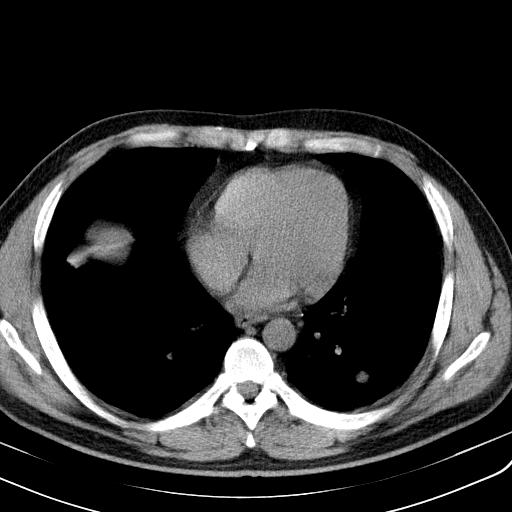

肺内纵隔多发结节,肺内以外周为著,首先考虑转移瘤

纵隔内多发肿大淋巴结,两非弥漫性小结节状病灶,分布范围为肺外围为主,首先考虑为肺内和纵隔内转移性病变。(前不久我科室就遇到一女性38岁,肺癌伴肺内弥漫性转移)

双肺散在多发类圆形结节灶,边缘较光滑,纵隔淋巴结肿大,考虑转移瘤

淋巴结近呈对称性肿大,肺部多发结节,首先考虑结节病,其次考虑转移瘤。

肺内多发大小不等结节影,以外周为著,纵隔见多个淋巴结肿大;结果病人,35岁,有发烧咳嗽等病史,首先考虑血源性肺脓肿可能性大,建议积极抗炎治疗后复查,除外转移瘤或韦格氏肉芽肿.